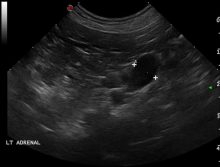

CT Visualisation of Deep Vegetal Foreign Bodies

Diagnostic Imaging |

Soft Tissue Referral Team take advantage of the Diagnostic Imaging Department for the visualisation of deep vegetal foreign bodies ...